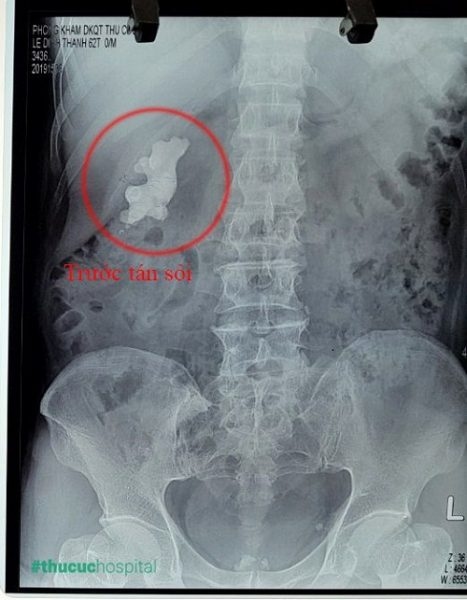

Ngày 22/07 ca tán sỏi đầu tiên bắt đầu. Sau 2 tiếng, một nửa “củ gừng” – tảng sỏi san hô ở thận trái đã được loại bỏ. Lần tán sỏi tiếp theo được tiến hành sau đó 4 ngày. Lần này, bác sĩ Huyên cùng ekip đã xử lý thành công toàn bộ phần sỏi còn sót lại. Sang ngày thứ 5, bệnh nhân L.Đ.Thanh đã hoàn toàn tỉnh táo, các chỉ số sinh tồn ổn định, có thể tự đi lại, nói chuyện. Hai túi đựng vụn sỏi được bệnh nhân xin giữ lại làm kỷ niệm. Anh chia sẻ với mọi người rằng cuối cùng có thể thở phào nhẹ nhõm vì không còn lo sỏi thận nữa.

- Tảng sỏi thận 7cm đã được làm sạch hoàn toàn sau 2 lần tán sỏi nội soi qua da đường hầm nhỏ.

Về phía đội ngũ các bác sĩ, đây là thành quả cho sự nỗ lực của cả ekip. “Rất vui khi người bệnh chỉ phải tán 2 lần đã sạch sỏi trong khi dự kiến ban đầu phải 3 lần”, bác sĩ Phạm Huy Huyên nói. Đặc biệt bác sĩ chỉ cần tạo 1 đường hầm duy nhất nhưng vẫn tán được toàn bộ tảng sỏi ở các vị trí bể thận, đài trên và đài dưới. Trong khi đó với các trường hợp sỏi san hô kích thước lớn như thế này thông thường sẽ phải làm 2 đường hầm.